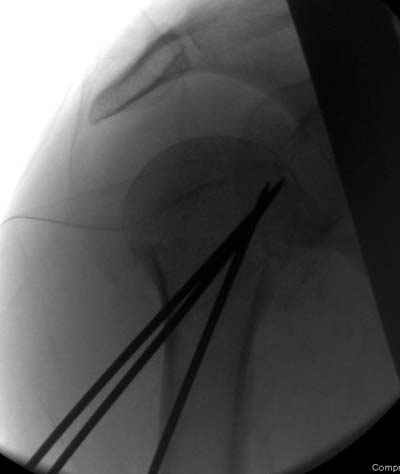

Женя, а как ты водишь спицы, в смысле, как делаешь входное отверстие, и как в него проводишь V-спицу? А то о дна из спиц, та, у которой не дошла до головки одна палочка буквы V, как-то выглядит на рентгенограмме, как будто или через очень большое отверстие введена, или каждая половинка через отдельные отверстия.

Мне кажется, проблема в том, что не все концы спиц зашли в головку, и зашедшие - недостаточно далеко прошли.

Спицы провожу по передней и задней поверхностям плечевой кости через 4,5 мм отверстия на разных уровнях.

Уточни - обе части буквы V вводишь в одно отверстие? А то по снимкам выглядит, что в разные.

V-спица проводится через 4,5 мм отверстие. Видимо, из-за разной длины вторая половина спицы *пролетела* мимо отверстия, что и привело к вторичному смещению костных фрагментов.